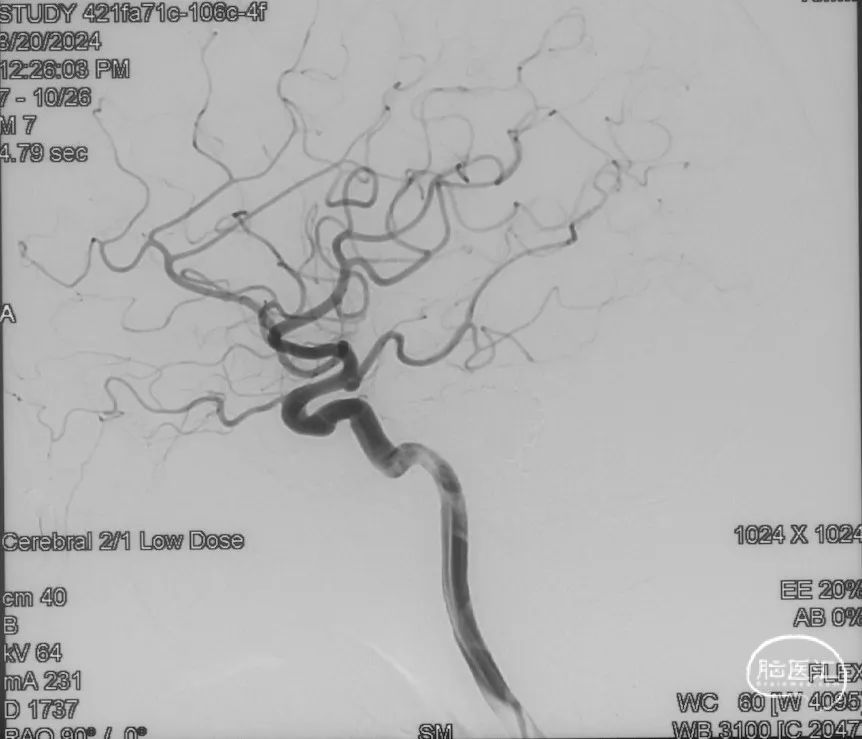

选取工作角度,正侧位造影

Echelon-10微导管在ASAHI 0.010微导丝导引下经右侧脑膜中动脉分支超选至瘘口,可见瘘口口径大,微导管直接越过瘘口,进入引流静脉起始部。

Marathon微导管在ASAHI 0.010微导丝导引下经右侧脑膜中动脉分支超选至瘘口近端。

经Marathon微导管手推造影明确微导管位于瘘口动脉端,Echelon-10微导管位于瘘口引流静脉起始端处扩张的静脉球内。

由于瘘口流量大,为了防止栓塞材料过度弥散,并逃逸至深静脉,首先通过Echelon-10微导管向静脉球内填入Feng 12/40、Feng 10/30两枚弹簧圈,限制后续液态栓塞材料仅在静脉起始部弥散。

随后回撤Echelon-10微导管,并通过Echelon-10微导管和Marathon微导管交替注入Onyx-34、Onyx-18,此时可见Onyx首先被血流冲至静脉球内,但被弹簧圈篮筐限制,并在瘘口范围内弥散。

通过“注射-停顿-再注射”,Onyx进一步在瘘口及供血动脉段和引流静脉起始部弥散满意

造影显示瘘口不显影,无静脉早显。

双侧颈外、颈内动脉正侧位造影瘘口均不显影

双侧椎动脉造影未见瘘口显影,可见广泛皮层静脉瘀滞

Onyx胶铸型显示瘘口形态。